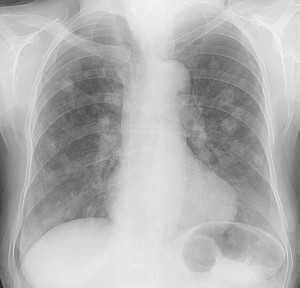

Рентгенография легких при тэла

Патологические изменения на рентгенограммах органов грудной клетки обнаруживаются в большинстве случаев ТЭЛА, однако не являются специфическими. Наиболее часто определяющиеся на рентгенограммах патологические изменения включают в себя ателектаз (спадение) части легкого, плевральный выпот, снижение прозрачности легочной ткани, а также высокое стояние правого или левого купола диафрагмы. Классическими рентгеновскими признаками инфаркта легкого является наличие затемнения клиновидной (треугольной) формы, широким основанием обращенного к плевре, верхушка которого направлена к корню легкого (бугорок Хэмптона), либо уменьшение выраженности сосудистого легочного рисунка в зоне тромбоэмболии (симптом Вестермарка).

Другими изменениями на рентгенограммах, обнаруживаемыми при ТЭЛА, являются расширение центральной легочной артерии с резким ее обрывом - «обрубленные корни», увеличение размеров сердца (особенно его правых отделов), а также признаки отека легких. Эти изменения могут сочетаться с острой клинической симптоматикой легочного сердца. Отсутствие изменений на рентгенограмме органов грудной клетки у пациента с выраженным нарушением дыхания и гипоксемией, но без признаков бронхоспазма, либо атипичного кровотока в сердце, крайне подозрительно на ТЭЛА. В целом, рентгенография органов грудной клетки не может использоваться для того, чтобы подтвердить или опровергнуть диагноз ТЭЛА; тем не менее, рентгенография и ЭКГ могут быть полезны для подтверждения альтернативного диагноза.